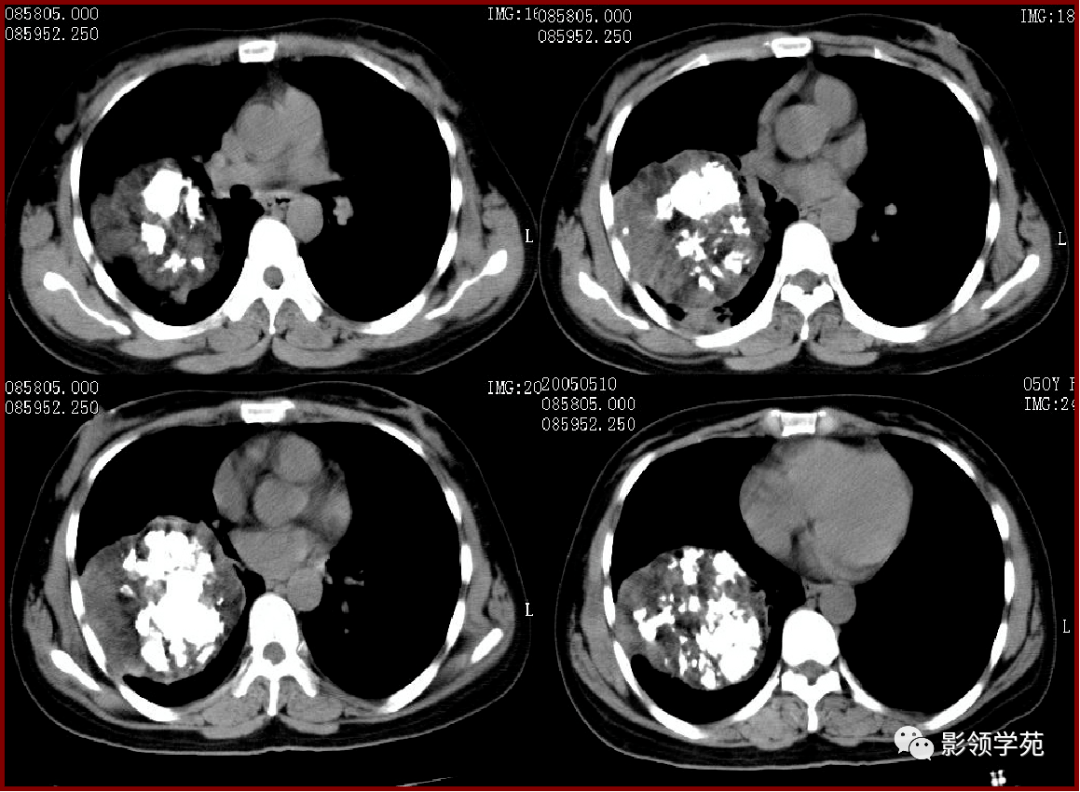

刘懿博士说肺癌(三〇八亖)肺良性占位长大也会咯血,要及时切掉

图片尺寸1600x1227